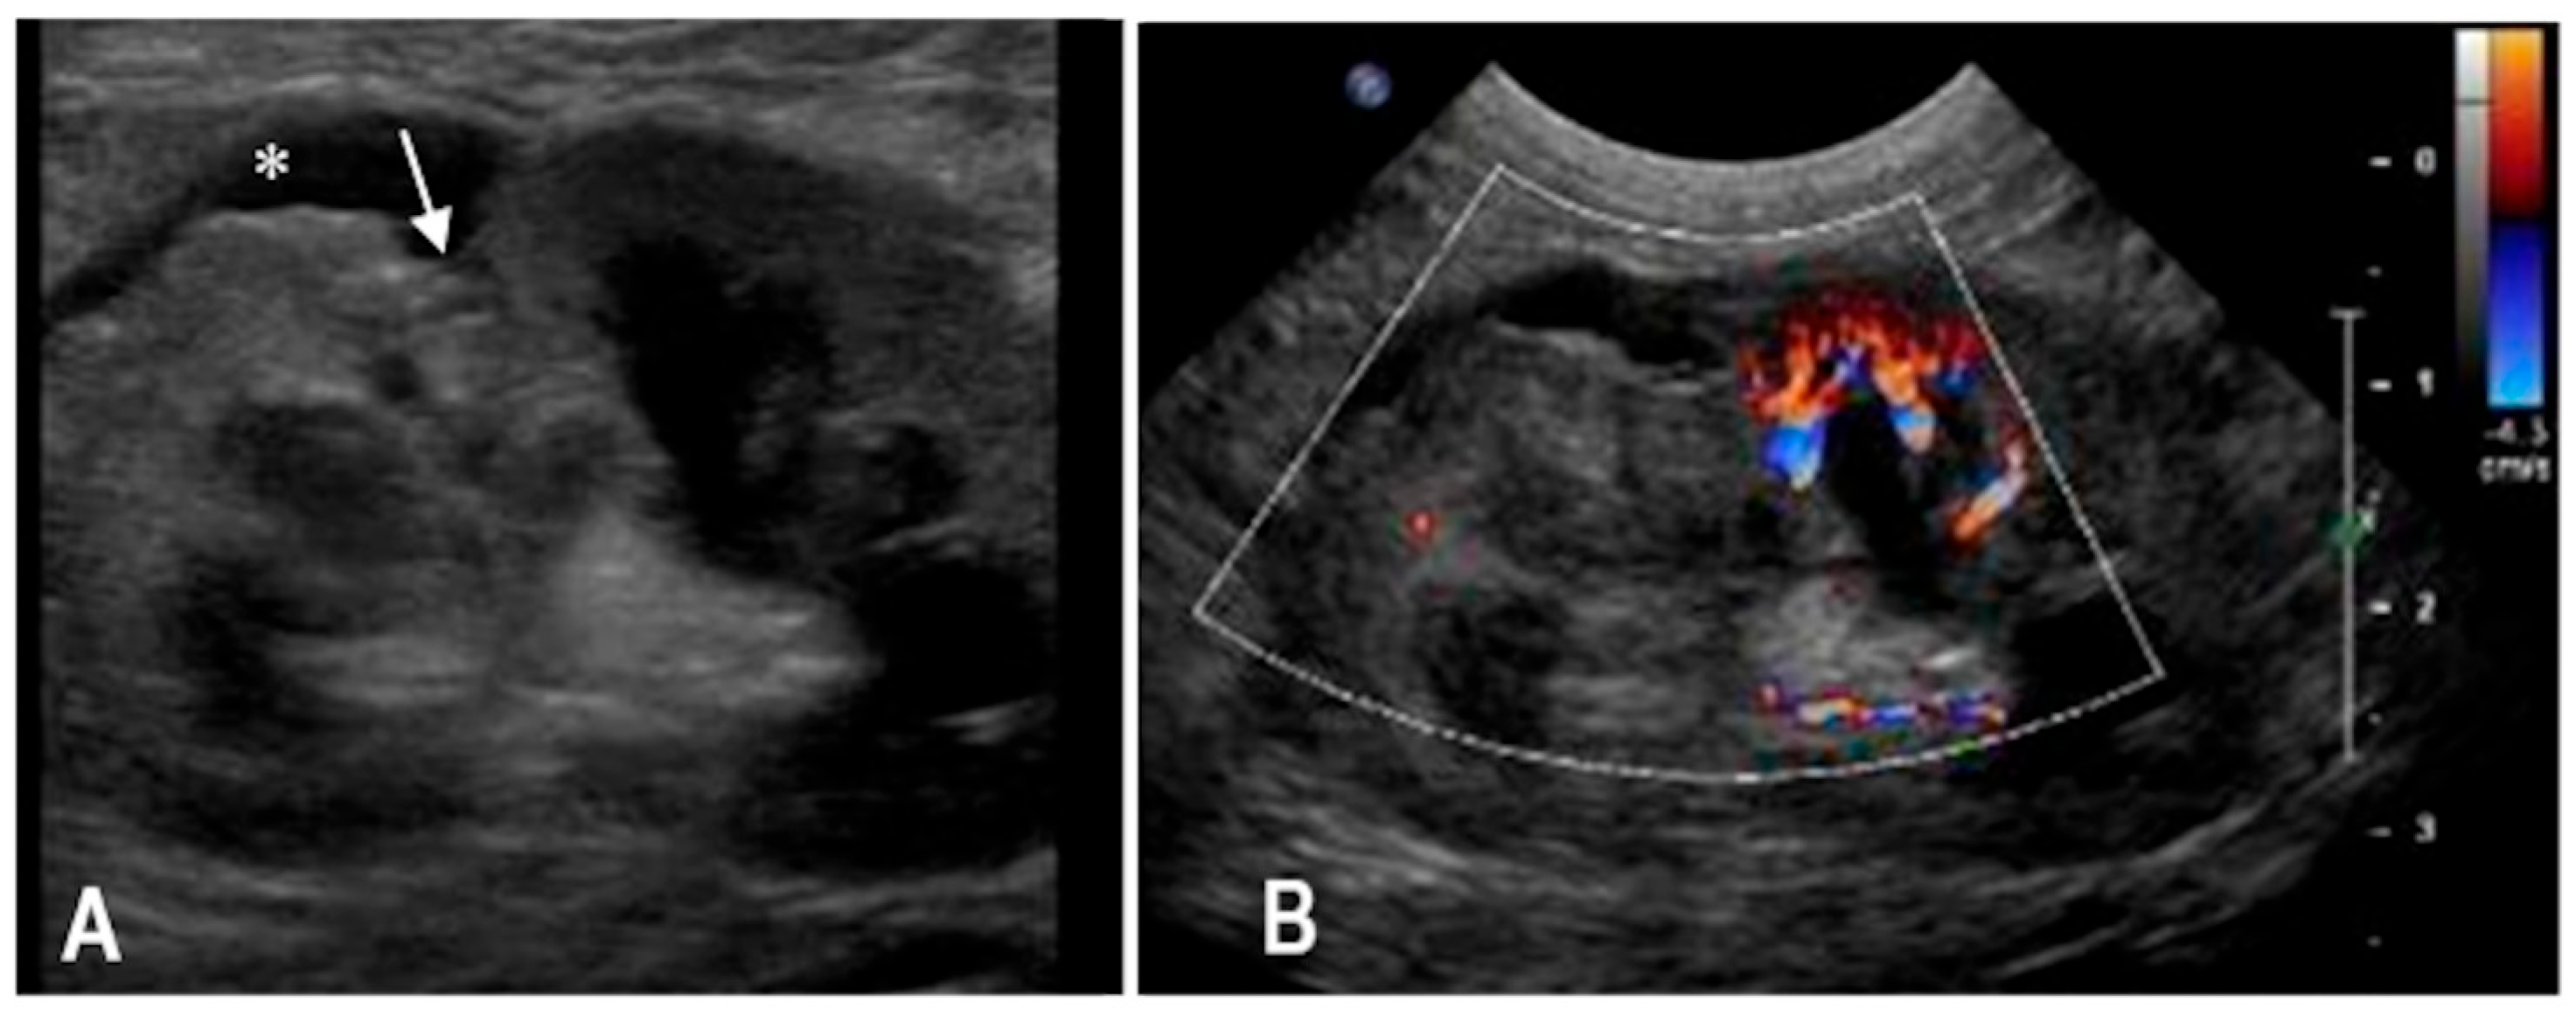

3.1. Case 1